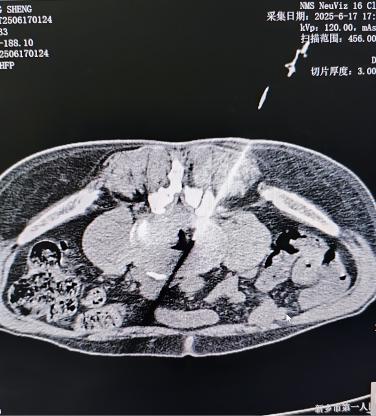

腎結石/泌尿系統(tǒng)問題:當結石卡在輸尿管或腎臟發(fā)炎時,疼痛可劇烈放射至同側腰肋部,常伴隨血尿、排尿異?;虬l(fā)熱。這種疼痛通常與腰部活動關系不大,卻可能陣發(fā)性加劇。

其他內臟疾?。喝缗枨谎?、附件炎、胰腺炎、主動脈瘤、腹部占位等,有時也會以腰痛為表現(xiàn),需結合其他癥狀綜合判斷。